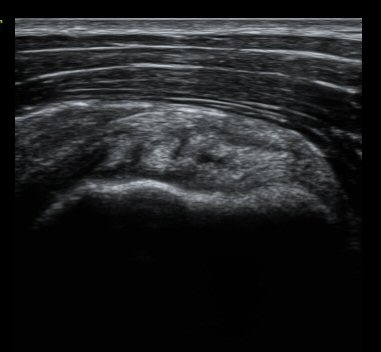

±Ø»ó°Ç Á¾´Ü¸é°Ë»ç¿Í Ⱦ´Ü¸é°Ë»ç¿¡¼­ ±Ø»ó°Ç³» ¹Ì¼¼ÇÑ °£±ØÀÌ °üÂûµÊ(±×¸² 6, 7, 8).